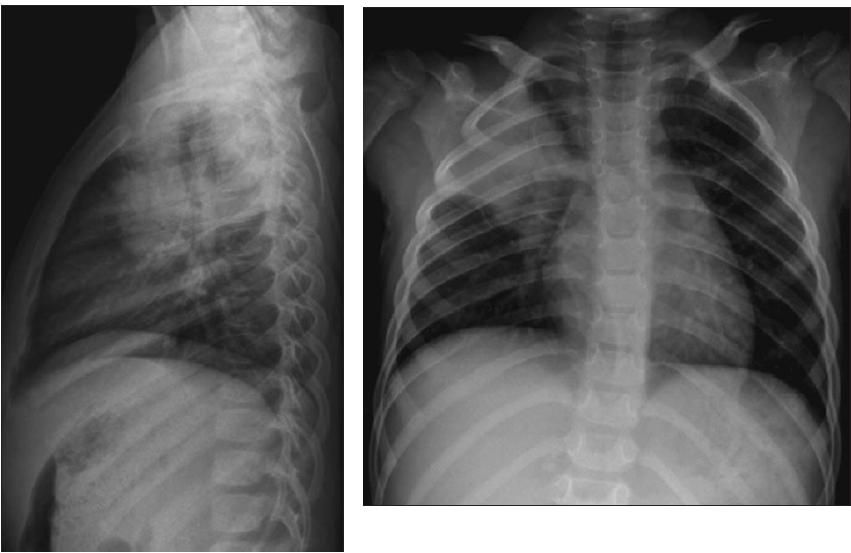

5. One more study was obtained. (Perhaps you already thought to order it, back at Question 2.) Do these images explain the patient's right upper quadrant pain? (A is the correct choice.)

The chest radiographs reveal the culprit. The patient has a dense right upper lobe infiltrate. Her pneumonia presented as acute abdominal pain-a known confounder in evaluation of a child who is ill with pneumonia. Many times this phenomenon is seen with a lower lung infiltrate, which is then detected at the upper portion of the abdominal radiographs. The films should always include the lung bases. In this child's case, the upper lobe pneumonia was just beyond the upper edge of the abdominal images. Even when we reviewed the scout image from the abdominal CT scan, the infiltrate could not be seen. (Elementary, my dear Watson!)